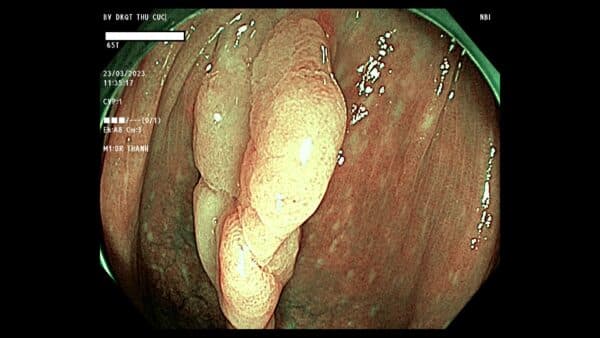

Polyp đại tràng là tổn thương nhỏ ở bề mặt, có thể có cuống hoặc không cuống. Phần lớn polyp đều là lành tính nhưng vẫn có trường hợp polyp biến đổi tế bào, phát triển kích thước lớn thành ác tính nên không thể chủ quan. Polyp lớn có thể gây nhiều biến chứng nguy hiểm như xuất huyết tiêu hóa, tắc ruột, thậm chí là ung thư đại tràng.

Cận cảnh hình ảnh một polyp đại tràng được phát hiện khi người bệnh thực hiện nội soi đại tràng.